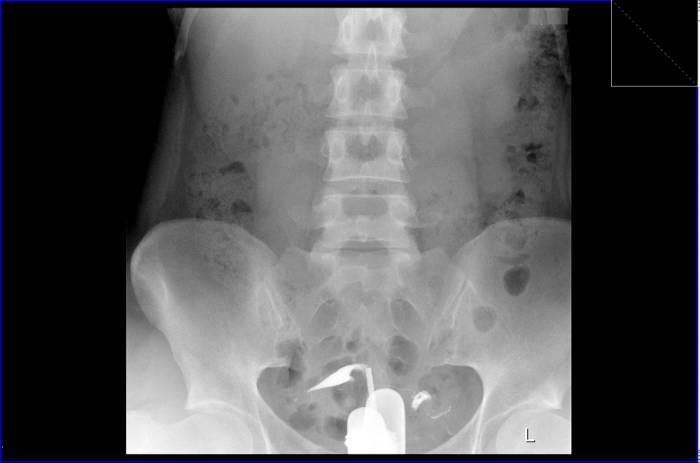

Левая маточная труба свободно проходима.

Правая маточная труба в интрамуральной области непроходима.

Стрелка показывает наличие препятствия в устье правой маточной трубы.

Буква «R» на изображении обозначает правую сторону пациента.